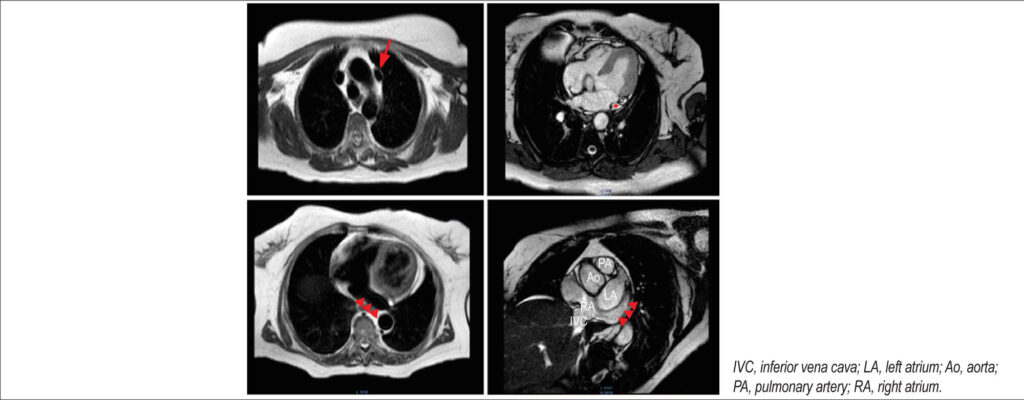

A 72-year-old woman with hypertension was admitted for sudden cardiac arrest secondary to idiopathic ventricular fibrillation. Cardiac magnetic resonance disclosed a persistent left superior vena cava (PLSVC) without other cardiovascular abnormalities for which an implantable cardioverter-defibrillator (ICD) was proposed with left access. Intraoperatively, cephalic vein cannulation placed the wire in the PLSVC that drained in the coronary sinus and subsequently the right atrium. A wide loop maneuver placed the lead tip facing the tricuspid valve, and right ventricle access was obtained with successful positioning of the ventricular lead. Device parameters were checked and considered suitable, and the procedure was finalized with active fixation, a fluoroscopy time of 1.35 minutes, and a radiation dose of 143.12 μGy/cm2. Normal pacing parameters were present at the 3-year follow-up.

PLSVC is a congenital venous anomaly present in 0.5% of the general population that is usually asymptomatic and incidental on invasive procedures or imaging. Although not a contraindication to ICD, lead placement is challenging because it has to negotiate two bends, one at the coronary sinus and the other in the tricuspid valve. Stylet shaping or wide loop techniques are reliable and present good outcomes not affecting pacing parameters on long-term follow-up.